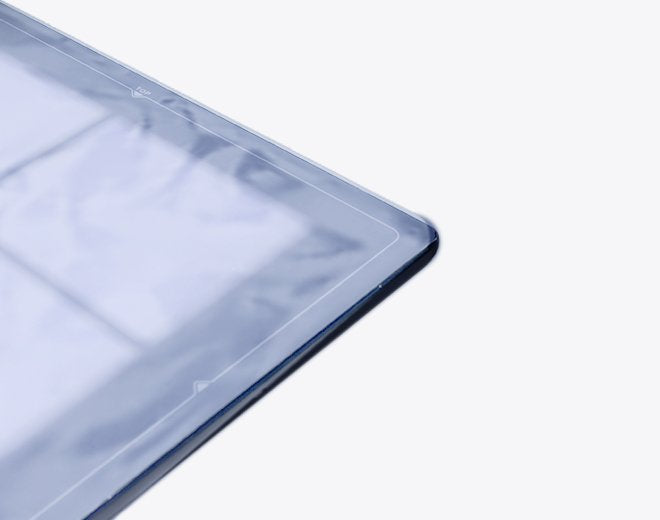

Gigantic Bag’s X-Ray Cassette Covers are designed to protect x-ray cassettes from damage and contamination, ensuring safety and cleanliness in medical environments. These single-use, disposable covers are made from durable, fluid-impervious polyethylene plastic, providing an effective barrier to stop the spread of infection and protect equipment from fluids. Ideal for use in emergency rooms, operating rooms, or with portable x-ray units, these covers deliver trusted performance when it matters most.

- Single-Use and Disposable: Designed for one-time use to maintain hygiene and prevent cross-contamination.

- Durable Construction: Made from top-grade 4-mil polyethylene plastic, ensuring strength and reliability.

- Fluid Impervious: Provides an effective barrier against fluids, safeguarding equipment and preventing damage.